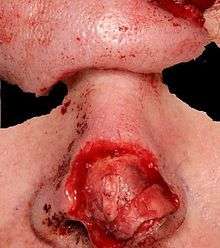

The flap is incised and elevated from distal to proximal.[1][3] Distally, the frontalis muscle and subcutaneous tissue are excised, this is done for 1.5 to 2 cm.[1][3] Then more downwards the disscection goes through the muscle and over the periosteum.[1] When reaching the brow, all of the skin borders are incised and the flap is carefully released.[1] As soon as the flap reaches the defect without tension further incision of the flap is stopped and the flap is inset into the area of the defect.[1][3][4] This is done using a single layer of fine suture.[1]

The flap is incised and elevated over the periosteum from distal to proximal.[1] The flap consists of skin, subcutaneous tissue, fat and frontalis muscle and is not thinned. When reaching the brow, all of the skin borders are incised and the flap is carefully released.[1] The full-thickness flap is then sutured into the defect without tension.

Three to four weeks later, when the full thickness forehead flap is well healed at the repicient site, the second stage begins. The skin of the flap and 3–4 mm of subcutaneous fat is elevated.[1][3] The underlying excess of soft tissue is then excised and the remaining healed tissue is sculpted in an ideal nasal subunit. The flap is then resutured to the repicient site.